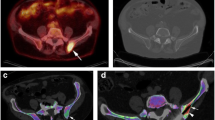

Qualitative image analysis on VNCa images has been found to improve diagnostic yield compared to monoenergetic CT alone. Like skeletal metastasis, myeloma lesions appear hyperattenuating on VNCa images. A prospective study examined using VNCa images with color-coded overlay maps to identify bone marrow lesions [30]. The study comprised 34 patients with either multiple myeloma or monoclonal gammopathy of unknown significance (MGUS) who underwent DECT and MRI. There was improved sensitivity of detecting bone marrow lesions on VNCa color-coded overlay maps (91.3%) compared to standard monoenergetic CT imaging (69.6%). Another prospective study also found a higher sensitivity of detection on color-coded bone marrow VNCa images, but only for non-osteolytic bone marrow lesions (78.9%) compared to monoenergetic CT (24.8%) [33]. The difference in detection sensitivity was even greater for non-osteolytic diffuse infiltration patterns of disease, with sensitivities of 75% on VNCa imaging compared to 0% on monoenergetic CT. There was no difference in detection sensitivity between the two types of imaging for multifocal infiltration patterns. Figure 5a–c are non-contrast DECT images with color-coded VNCa overlay reconstruction obtained from a patient with multiple myeloma at our institute. Figure 5d is the axial diffusion weighted imaging (DWI) MRI showing the location of the myeloma deposit in the left posterior ilium.

Axial non-contrast DECT examination in a male patient in his 60 s with multiple myeloma in a bone window, b soft tissue window, and with c color-coded VNCa overlay showing the areas of myeloma deposit (thick hollow arrow) in the left posterior ilium which appears as an area of increased attenuation (green on the color-coded overlay), compared to an area of osteopenia (thin arrow, appearing mostly blue) in the right posterior ilium that was initially suspected to have myeloma deposits as well. d Axial DWI MRI with a b value of 800 s mm−2 obtained on the same patient shows myeloma deposits in the left posterior ilium, but not the right posterior ilium

A technical report publication described using DECT in guiding bone biopsies on four patients [11]. Bone lesions were identified on MRI and/or PET but not easily seen on monoenergetic CT. DECT-guided biopsy was performed with the aid of VNCa images. Lesions were localized to regions of abnormal color-coding on the bone marrow VNCa images that corresponded with prior PET or MRI images. The authors reported beam-hardening artifacts from the needle but used the beam artifact to direct the needle trajectory (Fig. 6). Final VNCa images were obtained after sampling to confirm that the needle intersected the lesion of interest.

Axial imaging of a patient with acute myeloid leukemia. a T1-weighted spin echo fat-suppressed post-contrast MRI shows an enhancing lesion in the posterior right iliac wing (arrow). b Axial CT from the initial biopsy does not show the target lesion, with no lesion cells identified at pathology. c Axial DECT with three-material decomposition algorithm for bone mineral, yellow marrow, and red marrow, fused with a VNCa color map overlay demonstrates the lesion. d Axial DECT color map with the needle on the surface of the posterior iliac wing directed toward the lesion shows beam-hardening artifact (arrow). The orientation of the artifact indicates the biopsy tract and can be helpful in directing needle advancement. The final pathology report yielded acute myeloid leukemia. Reprinted by permission from Springer Nature License and